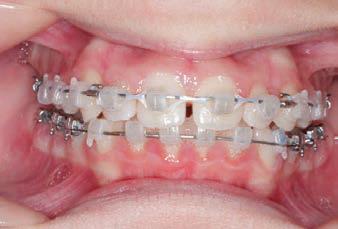

FINAL - 10/10/19 - Appliances removed AFTER

PROGRESS 7 - 10/10/19 - Final day in SLX 3D Clear Brackets BEFORE